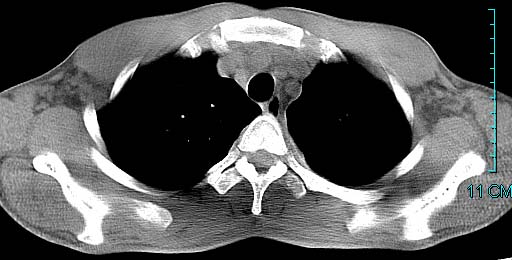

以下是引用ctkz987在2006-3-28 13:04:00的发言:[br]左侧胸腔积液穿刺后多发气液平(多房性),结合临床有高热不除外合并感染。

以下是引用qian在2006-3-28 14:32:00的发言:[br]左肺下叶大片状阴影,密度不均,见有条片影和空洞及气液平,少量胸腔积液伴有胸膜增厚,从图像看积液密度比水的密度高,结合病史,考虑左下肺化脓性炎症伴有脓胸。

以下是引用wawaquan在2006-3-28 22:25:00的发言:[br]左上肺舌段多发斑片影。结合“男24y咳嗽咳痰气促伴高热(38.5--39.5)20多天”及穿刺史,[br]考虑1 左下肺化脓性炎症;2脓胸。

以下是引用乡医在2006-3-28 18:37:00的发言:[br]左侧多发液气平面结合患者男24y咳嗽咳痰气促伴高热(38.5--39.5)20多天,查胸水:ldh239.3,总蛋白59.19,tb-ab阴性,利凡它试验+,红c2.7*109,白c1.08*109,分类淋巴92%分叶8%,考虑1脓胸2肺隔离征感染